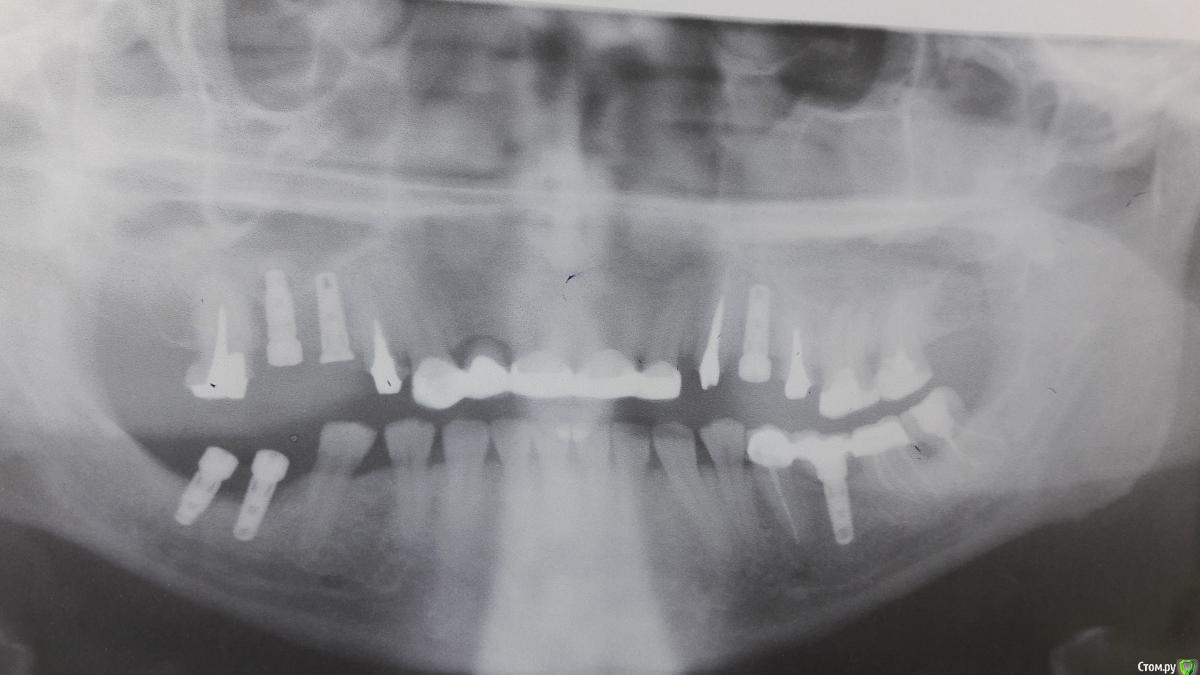

MaxDok Опубликовано 6 июля, 2016 Поделиться Опубликовано 6 июля, 2016 Устанавливали в Корее,когда доллар 40 был , сейчас дорого лететь . Коллеги , подскажите кто в России продаёт , если вообще продают . Нужно три аналога, три трансфера и абатметы .Не могу найти в интернетах,одна реклама . Ссылка на комментарий

MaxDok Опубликовано 7 июля, 2016 Автор Поделиться Опубликовано 7 июля, 2016 вроде зиммер с альфой и мисом совместимые платформы имеютСегодня проверил , от альфы трансфер подошёл. Ссылка на комментарий

Борис80 Опубликовано 12 июля, 2016 Поделиться Опубликовано 12 июля, 2016 платформа немного, но отличается. у меня правда от биогора были трансферы. импламакс тоже торгует ими. имплантаты там есть как обычные, так и танталовые. судя по 40 долл это не тантал, те дороже Ссылка на комментарий